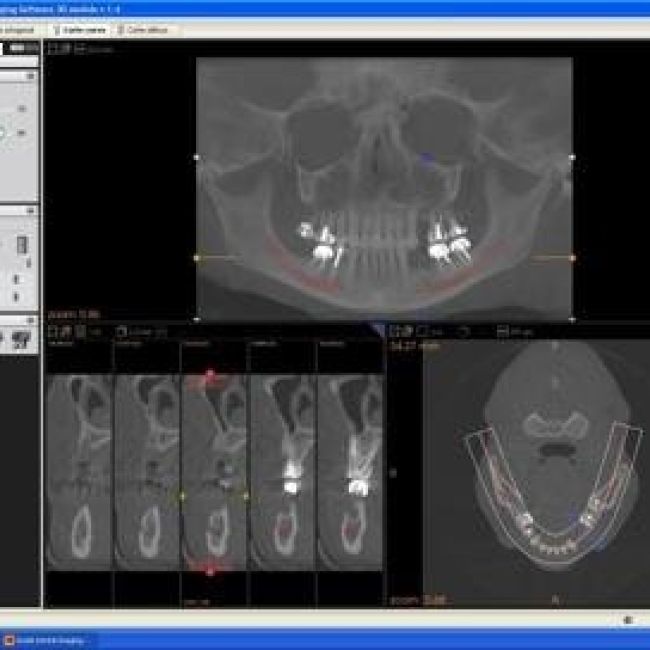

En los centros de Imagen Diagnóstica Dental Dr. Mayor ofrecemos una amplia variedad de servicios, gracias a la moderna aparatología con las que contanmos. Las pruebas diagnósticas que realizamos en nuestro centro son las siguientes: